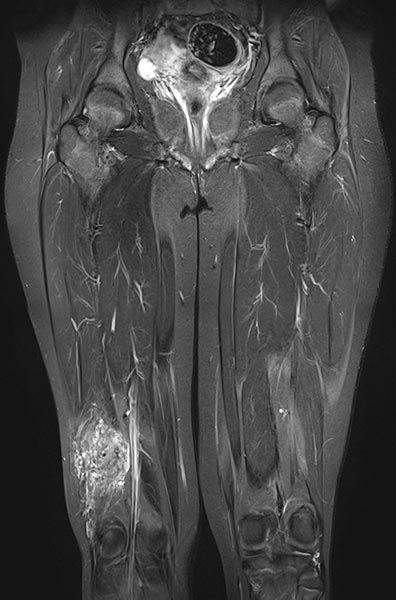

Coronal fat-suppressed T2-weighted MRI of the thighs shows an intramuscular venous malformation on the right thigh (hyperintense).